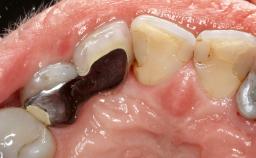

Treatment of Peri-Implant Mucositis at a Zirconia Implant